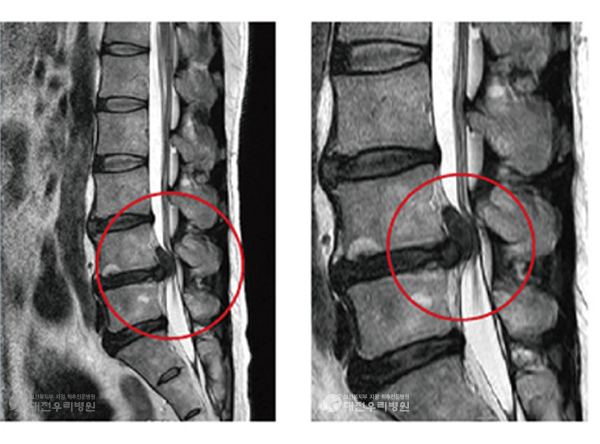

Ç㸮µð½ºÅ©´Â ôÃß »À »çÀÌÀÇ µð½ºÅ©°¡ Å»ÃâÇÏ¿© ½Å°æÀ» ¾Ð¹ÚÇÏ¸é¼ ÅëÁõÀ» À¯¹ßÇÏ´Â ÁúȯÀ¸·Î, ¾É¾Æ Àְųª Ç㸮¸¦ ¼÷ÀÏ ¶§ Áõ»óÀÌ ¾ÇȵǴ ¾ç»óÀ»

º¸ÀÌ´Â °æ¿ì°¡ ¸¹½À´Ï´Ù. ôÃß°üÇùÂøÁõÀº ³ëÈ¿Í °ü·ÃµÈ ÅðÇ༺ º¯È·Î ½Å°æÀÌ Áö³ª°¡´Â Åë·Î°¡ Á¼¾ÆÁö¸é¼ ¹ß»ýÇϸç, ¿À·¡ ¼ Àְųª °ÉÀ» ¶§ Ç㸮¿Í

´Ù¸® ÅëÁõ, Àú¸² Áõ»óÀÌ ½ÉÇØÁú ¼ö ÀÖ½À´Ï´Ù.